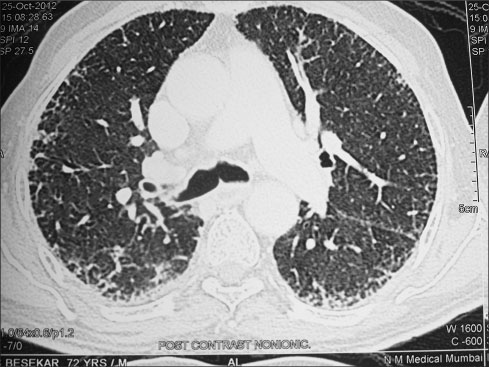

CT scans of the chest and radiograph of the chest [Figures 1], [2], [3] showed inter- and intralobular septal thickenings in the bilateral lung parenchyma predominantly in the lower lobes with peribronchial and fissural nodularity, suggestive of either sarcoidosis or ILD. The patient had a history of chronic cough till few months back which was self-limiting. There was no history of breathlessness, and he was moderately physically active before the present episode. His serum calcium and angiotensin-converting enzyme levels were normal, thus excluding sarcoidosis.

| Figure 2 Pretreatment chest X-ray